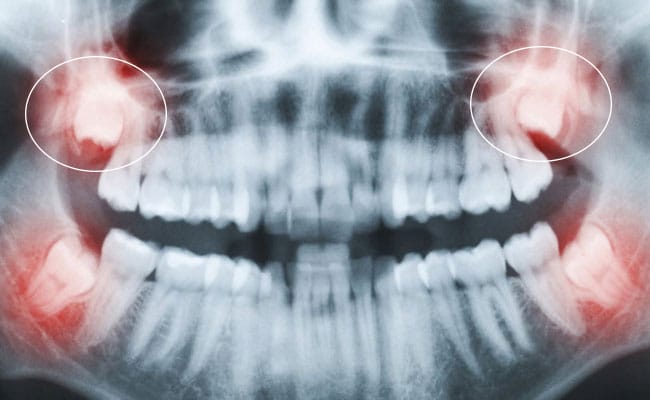

Răng khôn (hay răng số 8) là những chiếc răng mọc cuối cùng trên cung hàm, thường xuất hiện ở độ tuổi từ 17 đến 25. Hầu hết mọi người đều cảm thấy lo lắng khi nhắc đến chiếc răng này và băn khoăn “Có nên nhổ răng khôn không?”. Theo các chuyên gia nha[…]

Nhổ răng khôn là một trong những thủ thuật nha khoa phổ biến, nhưng nhiều người lo lắng liệu nhổ răng khôn có đau không, chi phí bao nhiêu, và nên thực hiện ở đâu tại Hà Nội để đảm bảo an toàn và hiệu quả. Trong bài viết này, chúng tôi sẽ giải đáp[…]